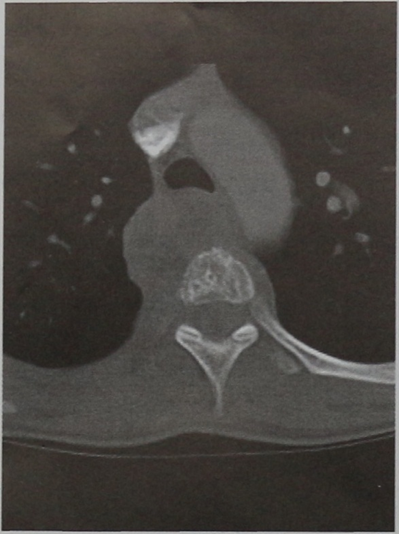

КТ грудного отдела позвоночника (горизонтальная проекция). Крупная опухоль мягких тканей в переднебоковой области позвоночника справа, сдавливающая трахею. Распространяется на дугу аорты.

КТ позвонка ТhVIII (горизонтальная проекция, костное окно). Распространенный остеолиз тела позвонка с околопозвоночным опухолевым образованием, идентичным по плотности мягким тканям.